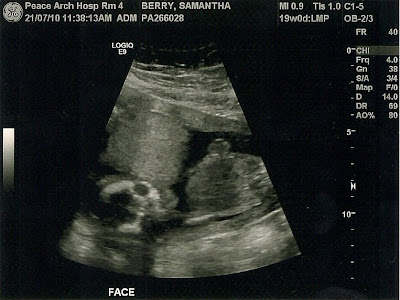

We had the ultrasound done this morning. Everything is great and the baby is very healthy. I was able to see it kicking like crazy like it was trying to swim. It moved around a lot and was hard to catch. Quite an amazing thing to see.

Since an ultrasound doesn't show the skin too well, I've nicknamed the baby skeletor.

We were also able to tell that the baby has really big hands and feet just like me.